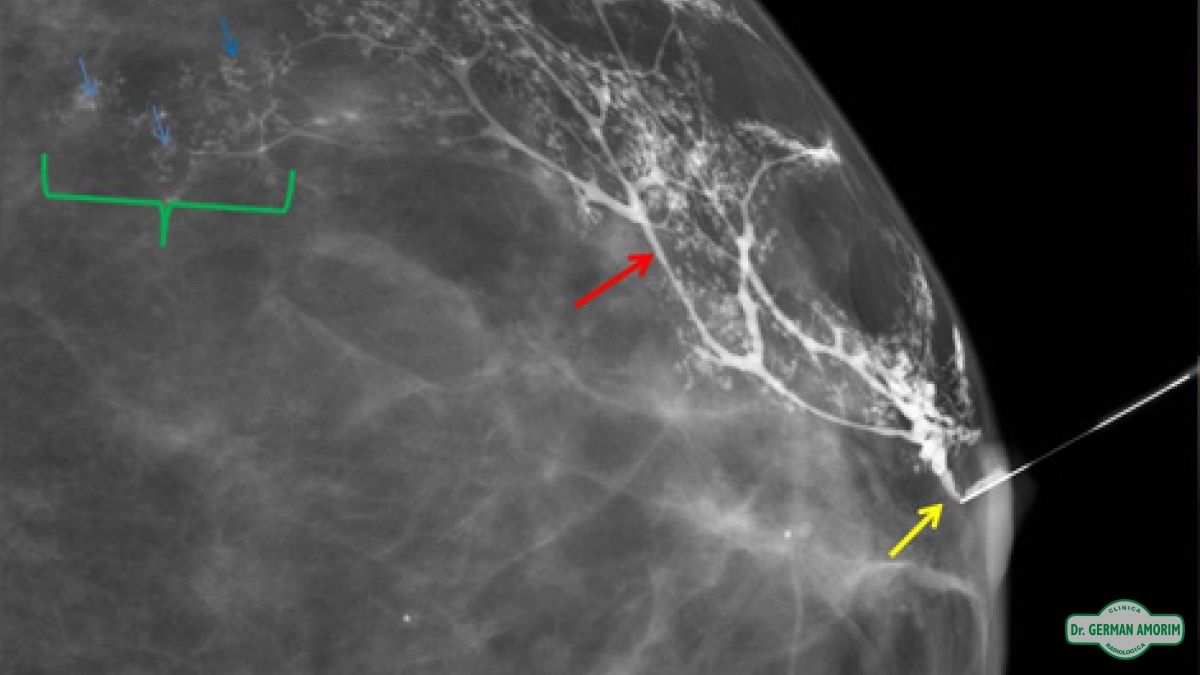

La lesión intraductal más frecuente es el papiloma y aunque el carcinoma intraductal tiene una frecuencia menor, al no poder distinguir entre ellas con este método de imagen, se recomienda la escisión quirúrgica. Es en este contexto que la galactografía sirve de mapa prequirúrgico para identificar correctamente el conducto patológico, la extensión de la lesión intraductal y la posible existencia de lesiones múltiples.

Entre las ventajas de esta técnica de imagen podemos mencionar la alta capacidad de definición de los ductos y de las posibles lesiones intraductales tras la administración de contraste, permitiendo así un mapa prequirúrgico para una escisión lo más selectiva posible.